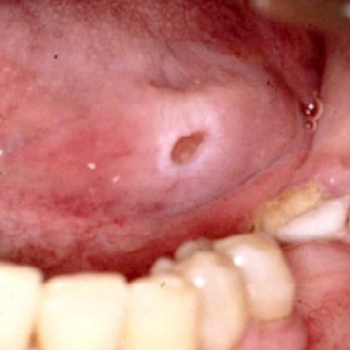

구내염은 세균이나 바이러스 등의 감염으로, 입 주변 및 입 안에 염증이 발생하는 현상입니다. 혀와 잇몸을 포함한 입안 점막등의 입안 쪽 염증 질환을 일컷습니다.

구내염 원인 2. 재발성 아프타성 구내궤양

원인은 정확히 밝혀진 것은 없으나 구강점박에 궤양이 생기는 구내염으로 세균, 바이러스 감염에 의한 것으로 알려져 있으며, 뜨거운 음식과 뺨 안쪽과 혀의 상처 등이 원인이 될 수 있으며, 피로와 스트레스, 알레르기 등에 의해 발생하기도 합니다.